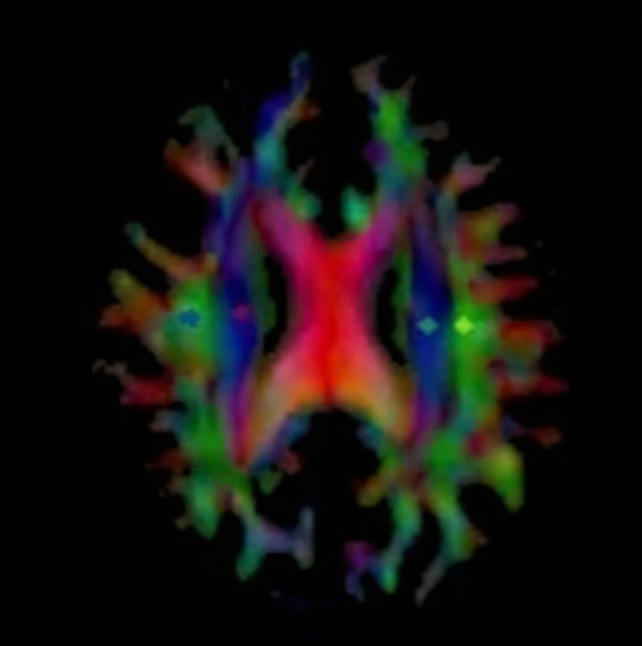

The study comes from researchers at the Osaka Metropolitan University in Japan, who tested the new Alzheimer's drug lecanemab on 13 people with the disease. Magnetic resonance imaging ( MRI) scans were used to look at the effects on the brain.